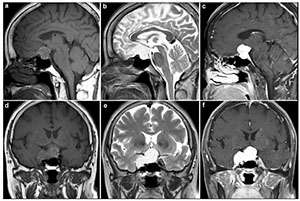

The lesion appeared iso-intense to gray matter on T1-weighted images (Figures 1a and 1d) and hyperintense on T2-weighted images (T2WI) (Figures 1b and 1e) and enhanced homogenously after gadolinium injection (Figures 1c and 1f). This imaging appearance was consistent with a pituitary macroadenoma. On T1-weighted MRI, the lesion was iso-intense or hypointense to grey matter and enhanced homogeneously after contrast administration. Suspecting a nonfunctioning pituitary macroadenoma, a transseptal transsphenoidal approach was used to remove the sellar tumor.

| Figure 1 Preoperative MRI revealed a large tumor in the sella turcica. a. The tumor has marked iso-intensity on a T1-weighted image in a sagittal view. b. The tumor has marked hyperintensity on a T2-weighted image in a sagittal view. c. The tumor is brightly enhanced in a sagittal view. d. The tumor has marked iso-intensity on a T1-weighted image in a coronal view. e. The tumor shows marked hyperintensity on a T2-weighted image in a coronal view. f. The tumor is brightly enhanced in a coronal view. |